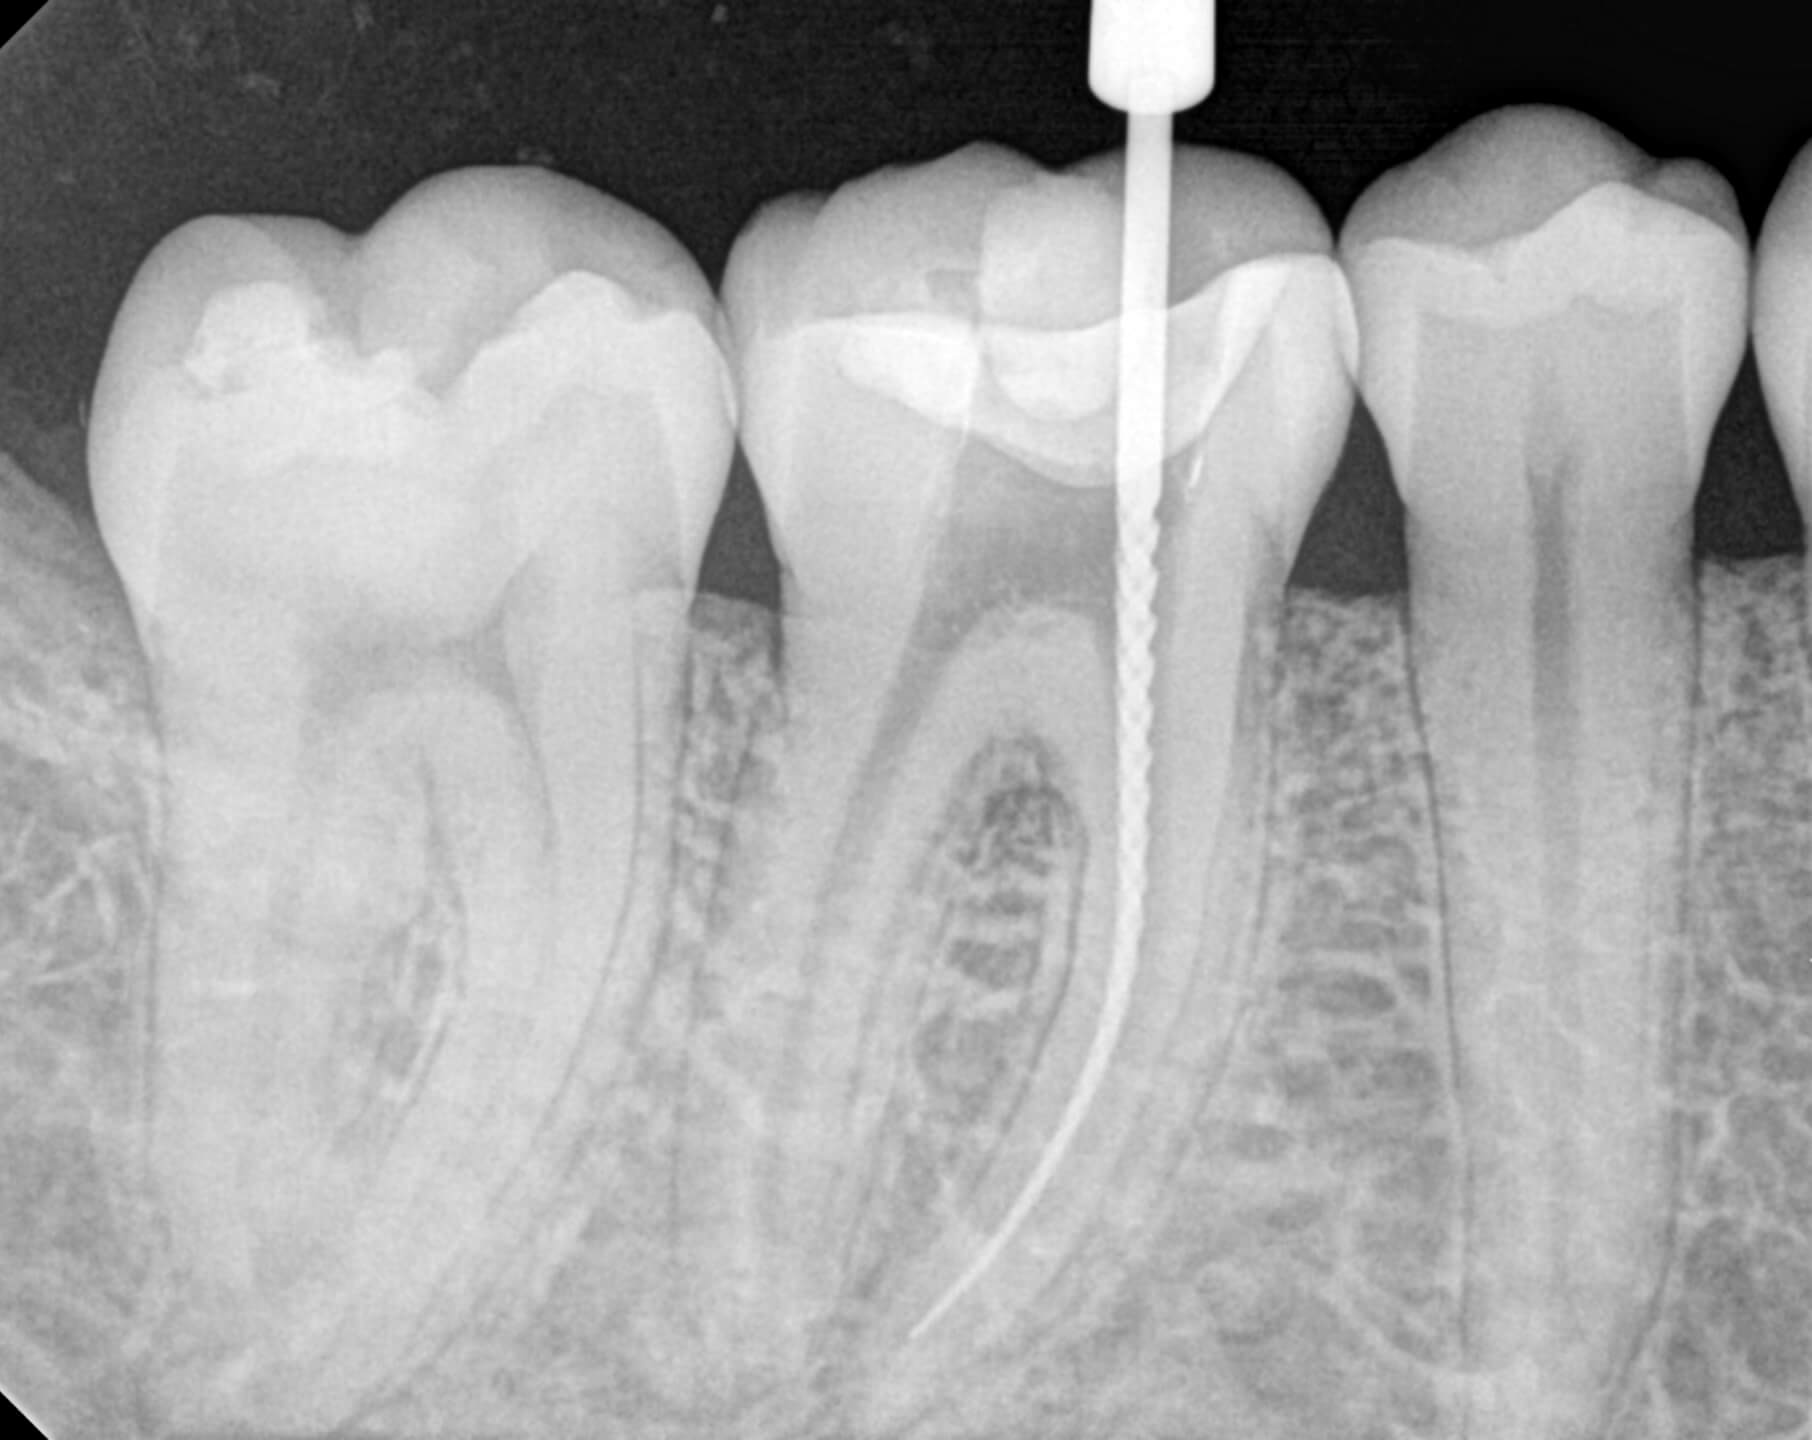

ENDODONŢIE

Este o specializare a medicinei dentare care se ocupă cu tratarea canalului radicular, pulpei dentare, precum şi a regiunii apicale a dintelui şi reprezintă o ramură importantă a stomatologiei pentru că durata de viaţă a dintelui depinde de corectitudinea acestui tratament: eliminarea tuturor bacteriilor care întreţin infecţia de pe întreaga lungime a canalului radicular.

În majoritatea cazurilor, tratamentul canalelor radiculare devine necesar în situaţiile în care dintele prezintă inflamaţie pulpară, în urma unei carii complicate.

Cele mai frecvente complicaţii ale cariei netratate sunt pulpita şi parodontita apicală, care duc frecvent la pierderea dinţilor. Dacă dintele nu este tratat, infecţia se răspândeşte la os şi la ţesuturile înconjurătoare.